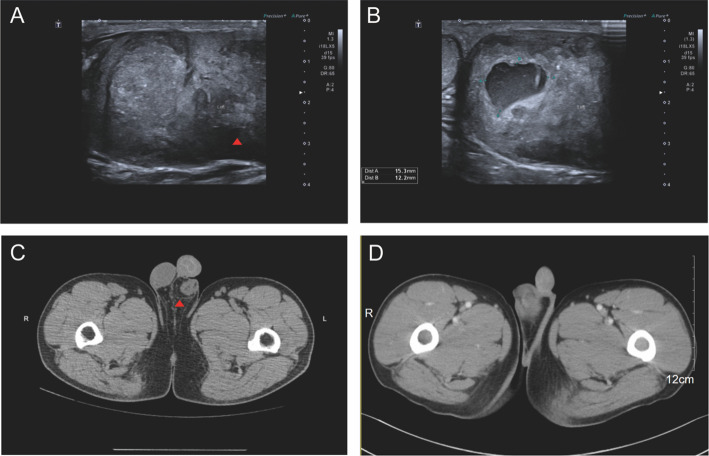

Case presentation: A 36-year-old male presented with painless left testicular enlargement. Ultrasound revealed a 6.0 × 5.0 × 3.3 cm heterogeneous mass with irregular vascularity. Initial pathological evaluation after radical orchiectomy at an outside hospital favored a diagnosis of seminoma. However, external consultation raised suspicion of ALK-negative anaplastic large cell lymphoma (ALCL) based on CD30 immunoreactivity. Further histopathological examination at our institution revealed tumor cells arranged in nests and solid patterns, with extensive inflammatory infiltration. Immunohistochemistry (IHC) demonstrated weak positivity for inhibin-α and diffuse positivity for CD30. Fluorescence in situ hybridization (FISH) confirmed EWSR1 gene rearrangement, leading to a final diagnosis of IN-SCT.